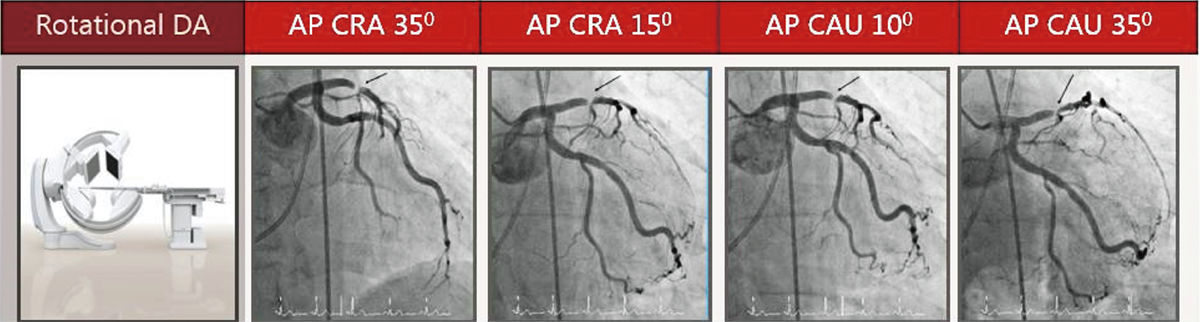

2D ротаційна ангіографія коронарних судин, виконується за одну ін’єкцію контрасту під час обертання C-дуги, та допомагає отримати діагностичні зображення коронарних артерій. Використання цієї технології дозволяє клініцистам отримувати зображення оптимальної якості зі зниженою дозою порівняно з традиційними методами отримання зображень. Автоматизоване послідовне поворотне отримання зображень допомагає клініцистам визначити пріоритезувати безпеку та ефективність.

Ротаційна коронарографія, що відображає стеноз судини під різними кутами, отримана під час обертання С-арки